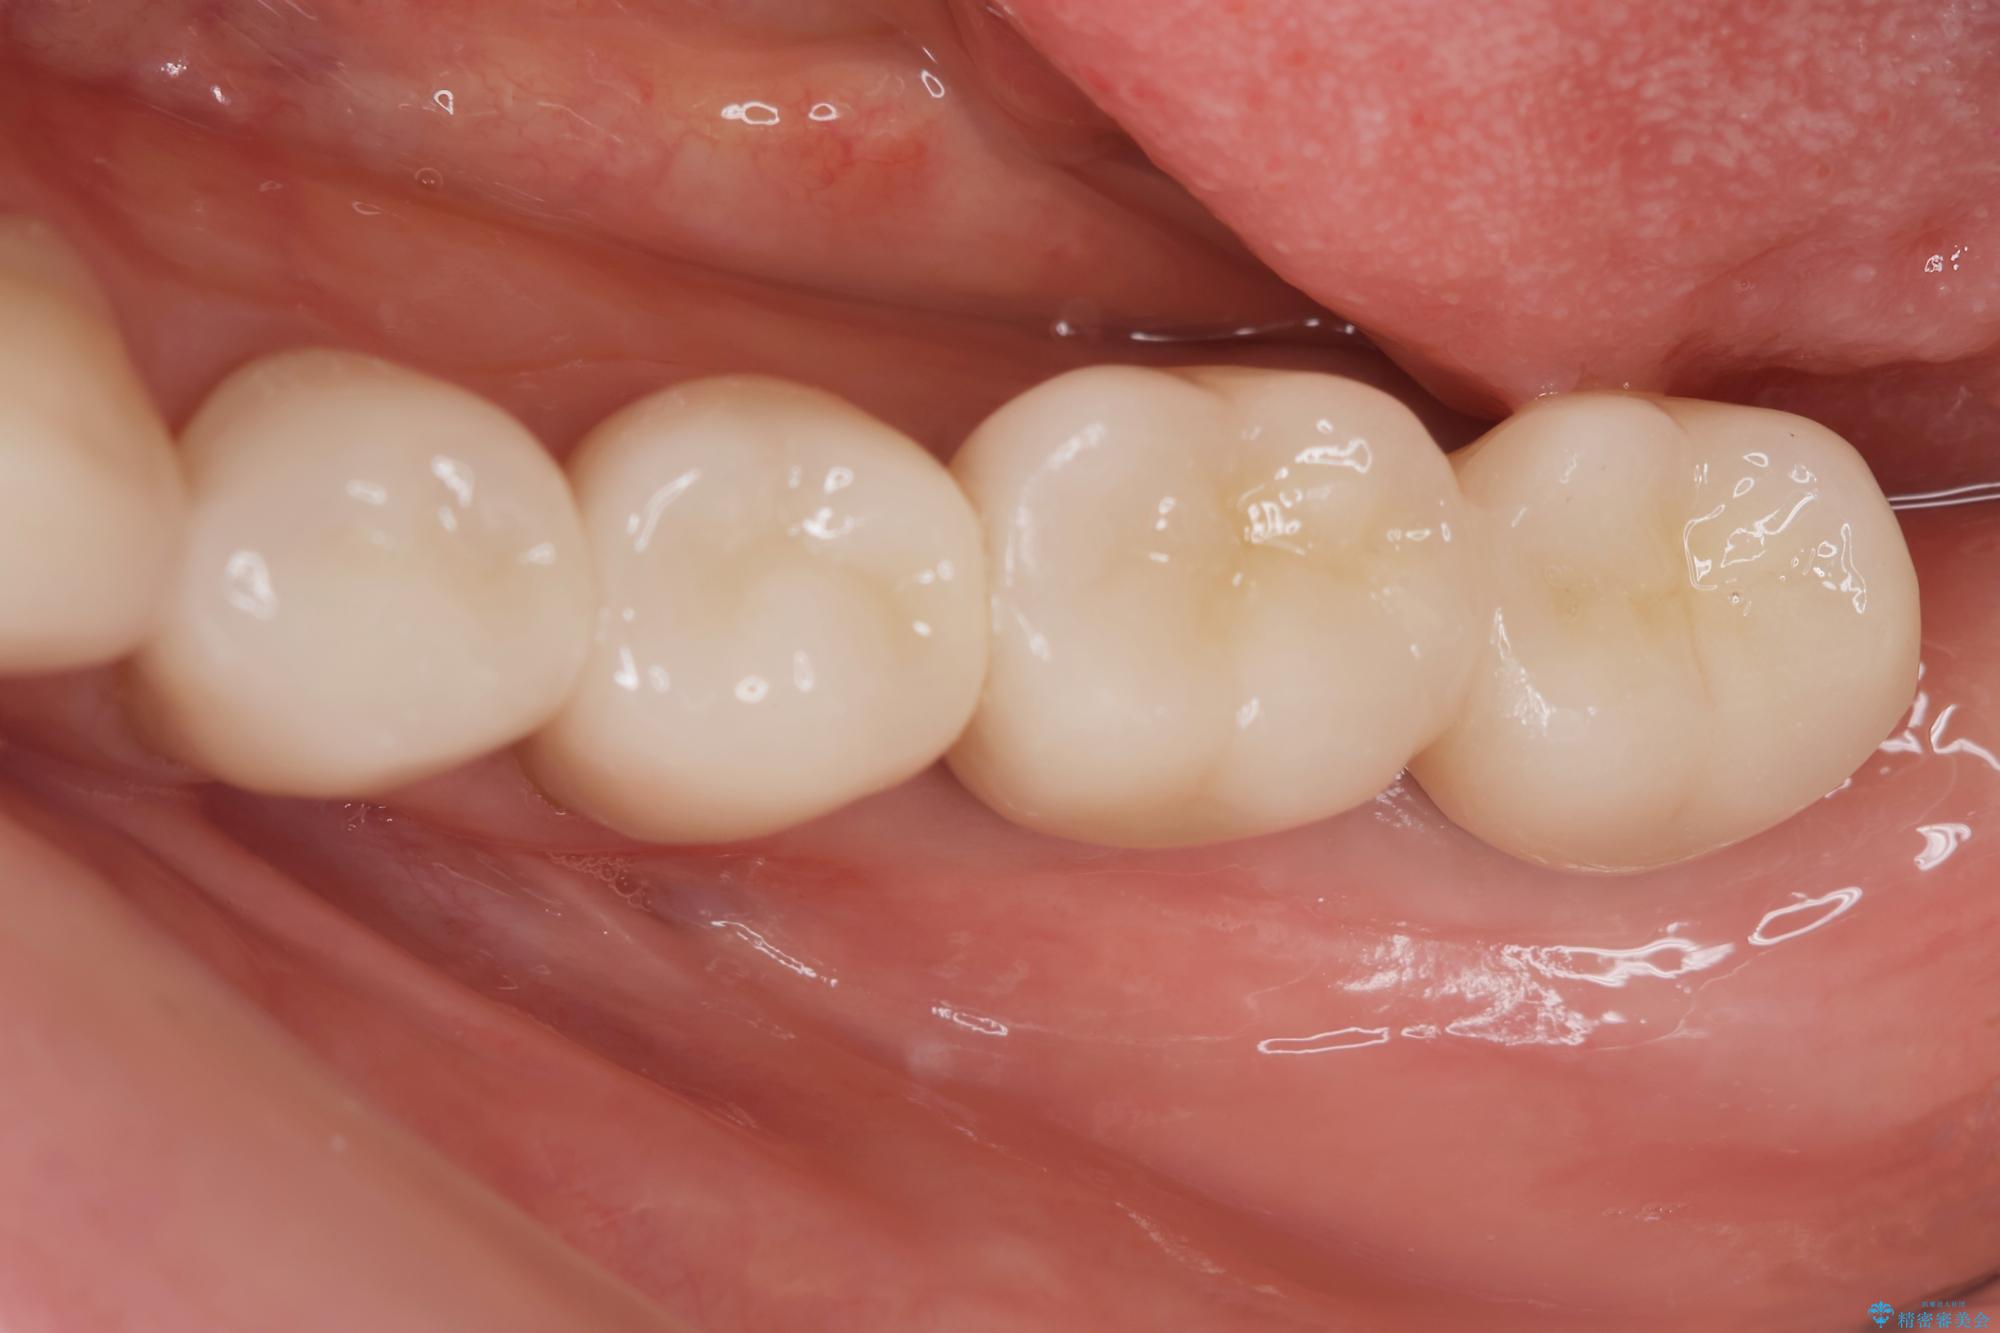

治療後

劣化の進んだブリッジの再治療[ 不適合な補綴物による虫歯の再発 ] 治療後画像 劣化の進んだブリッジの再治療[ 不適合な補綴物による虫歯の再発 ] 治療後画像 劣化の進んだブリッジの再治療[ 不適合な補綴物による虫歯の再発 ] 治療後画像